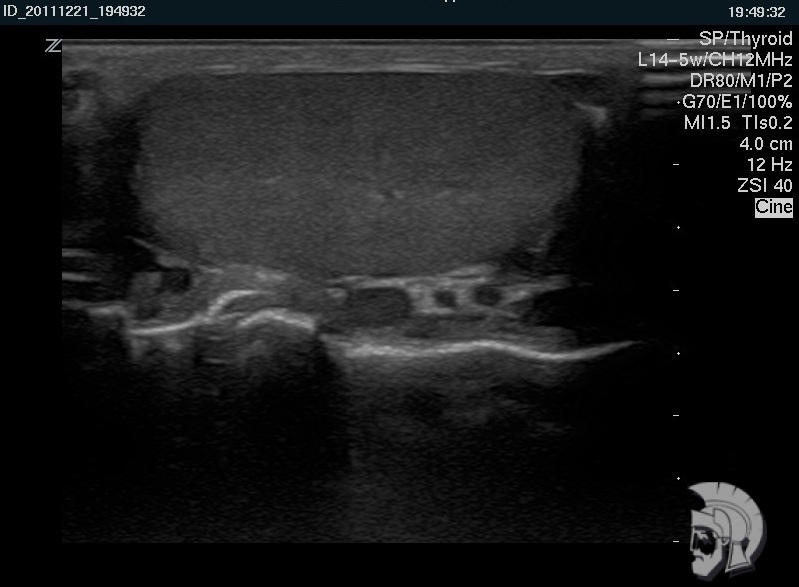

Фото УЗИ мошонки. Нормальная эхо-структура яичка мужчины 42 лет |